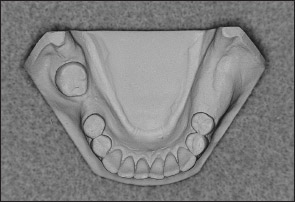

• Kennedy Class II arch: Displays a unilateral edentulous area located posterior to the remaining natural teeth (Figs 1-13 and 1-14).

Fig 1-13 Maxillary Kennedy Class II arch.

Fig 1-14 Mandibular Kennedy Class II arch.